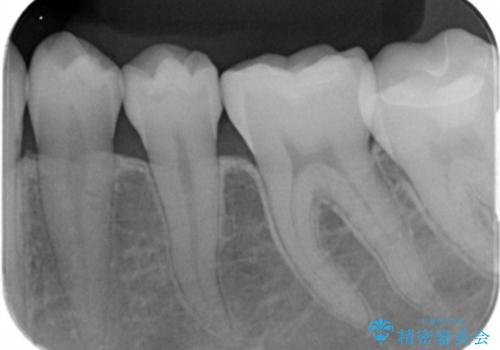

白い詰め物が入り患者様に満足して頂けました。

メタルインレーと比べてセラミックスのインレーは適合が良くて

虫歯の再発のリスクが少ないと言われています。